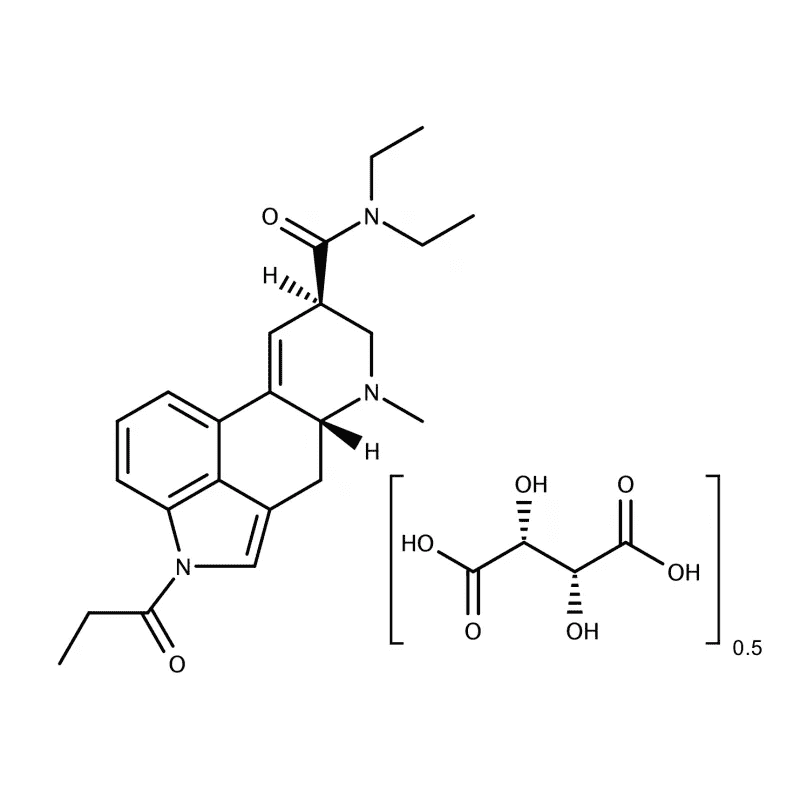

1-Propionyl-d-lysergic acid diethylamide (also known as 1P-LSD) is a semisynthetic compound of the lysergamide class. It is named for the propionyl group bound to the nitrogen of the polycyclic indole group of LSD. 1P-LSD is homologous to ALD-52, which holds an acetyl group bound to the nitrogen instead of the propionyl group bound at the same location. The structure of 1P-LSD contains a polycyclic group featuring a bicyclic hexahydro indole bound to a bicyclic quinoline group.